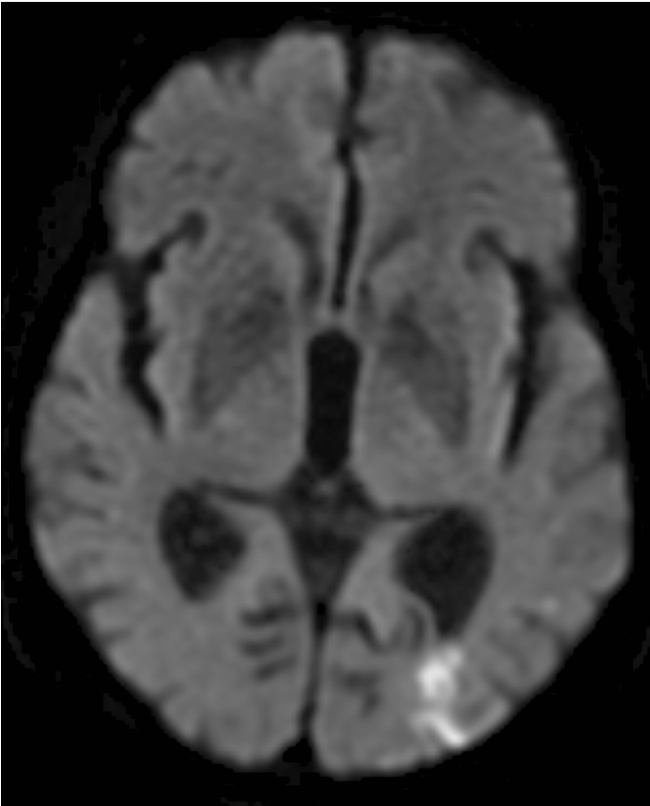

Border zone infarcts often tell a story. Unilateral cerebrum? Think proximal stenosis. Bilateral cerebrum & cerebellum? Think systemic event. In this case, nasopharyngeal ca → ICA occlusion → symptomatic border zone infarcts. See http://bit.ly/2Sdu5xa to learn more!pic.twitter.com/7fYYg8aReq